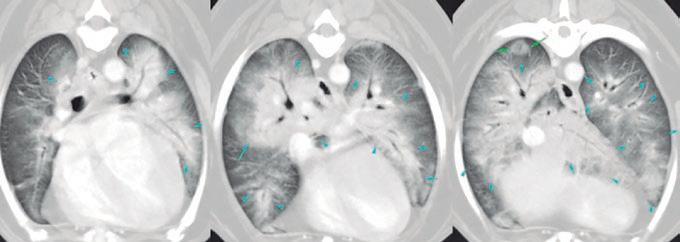

La radiología intervencionista es una especialidad que se encarga del diagnóstico y tratamiento de una gran cantidad de patologías de una forma mínimamente invasiva. Para realizar estos procedimientos es imprescindible disponer del equipamiento adecuado, tener nociones tanto de la instrumentalización como de las diferentes técnicas, y conocer con precisión la anatomía del paciente. Se trata de técnicas cada vez más implementadas en la clínica diaria ya que permiten solucionar diferentes patologías con una menor agresión a nivel tisular, una rápida recuperación, son procedimientos sin dolor, rápidos y seguros, suponen un menor coste respecto a otras cirugías invasivas, y constituyen una alternativa terapéutica a pacientes que no se pueden operar de forma convencional. Entre las más frecuentes destaca el cierre del conducto arterioso persistente, valvuloplastias en estenosis pulmonar, oclusión de shunts portosistémicos, implantación de marcapasos y colocación de stents

La radiología intervencionista, también conocida como radiología vascular e intervencionista, es una especialidad que se encarga del diagnóstico y tratamiento de una gran cantidad de enfermedades de una manera mínimamente invasiva. Se realiza mediante un abordaje guiado por distintas técnicas de imagen como, por ejemplo, la ecografía, la fluoroscopia o la tomografía computarizada, para alcanzar la zona a diagnosticar o tratar.

La radiología vascular e intervencionista ofrece una alternativa segura y eficaz a la cirugía en muchas enfermedades. Entre sus ventajas para el paciente destaca una menor agresión a nivel tisular, una rápida recuperación, procedimientos sin dolor, rápidos y seguros, un menor coste respecto a otras muchas cirugías con mis-